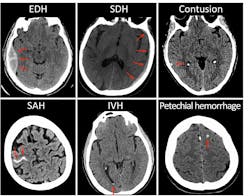

The researchers identified three distinct sets of patterns on the CT scans, indicating different types of damage after head injury which were associated with various outcomes. The results suggest that contusion (bleeding into brain tissue), subarachnoid hemorrhage (bleeding into the cerebrospinal fluid over the brain), subdural hematoma (bleeding between the brain and the thick covering over the brain), and intraventricular hemorrhage (bleeding into the fluid filled spaces in the center of the brain) were associated with worse outcomes 12 months after injury. Epidural hematoma, which describes bleeding between the skull and outer brain covering known as the dura, was associated with incomplete recovery at two weeks and three months, but was not linked to negative longer-term outcomes.